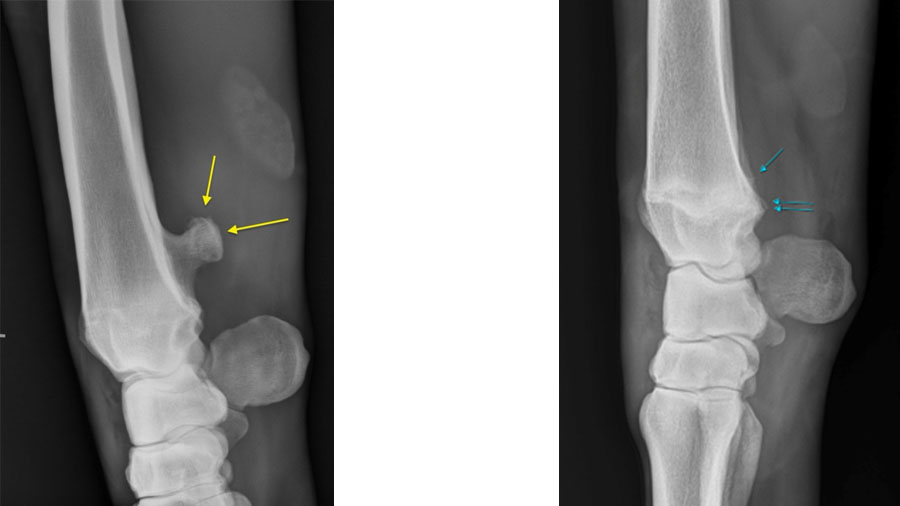

Radiography and ultrasonography are often used for primary investigation and can be easily misinterpreted.

Due to the concave aspect of the caudal radius at the level of the distal physis, axial spikes can be hidden by the more prominent medial and lateral extent of the physis, making them difficult to appreciate on standard projections. Equally, the medial and lateral physeal “scars” can be misinterpreted as spikes.

Representative clinical case

A recent case involved a 3‑year‑old Thoroughbred gelding with acute lameness and carpal sheath swelling, having successfully completed multiple races. Radiographs identified a large osteochondroma, and ultrasound confirmed marked disruption to the DDFT. Standard tenoscopic surgery was completed as above, identifying the osteochondroma extending deep into the DDFT. Removal was confirmed using radiography intra-operatively after debridement of the tendon lesion.